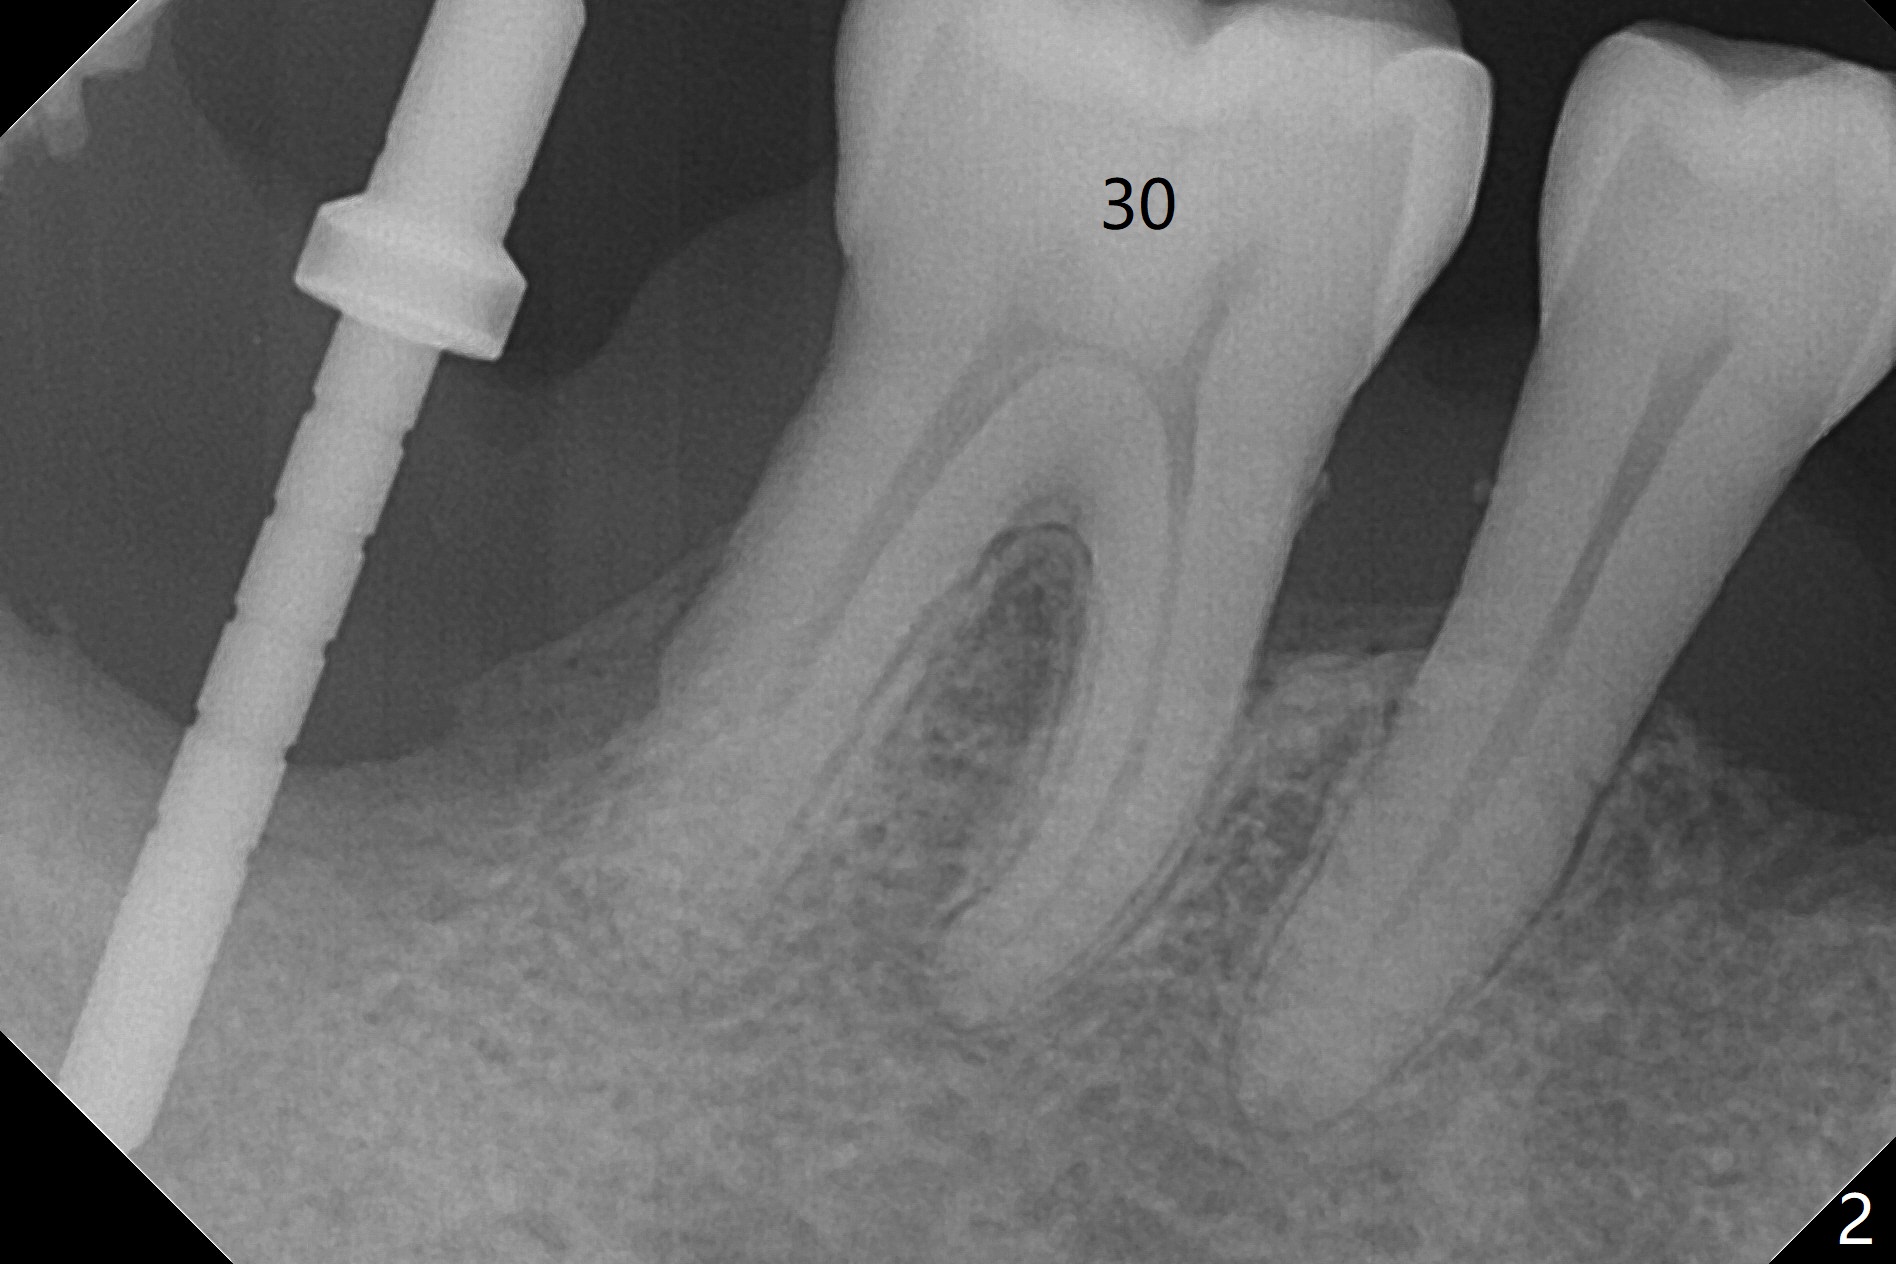

The affected tooth (#31, Fig.1) has severe buccal gingival recession with mobility III. After extraction and removal of granulation tissue, osteotomy is initiated in the middle of the fused socket using IS drills with 4 mm stopper (Fig.2,3). Following sequential osteotomy until 4 mm drill, a 4.5x10 mm IS dummy implant does not achieve primary stability, whereas 5x10 mm one does (Fig.4,5). Due to limited bone height confirmed intraoperatively, a shorter UF implant is placed with insertion torque 30 Ncm (Fig.6,7) with ~ 4.5 mm implant threads exposed coronally. After placing a 6.5x5(5) mm abutment, Vanilla Graft (*) and PRF membrane and collagen plug, an immediate provisional is fabricated to close the remaining socket. The tooth #32 is kept initially to increase the stability of the provisional and removed 8 day postop because of discomfort. A 5.5(2.5) mm mill abutment is changed to 3 months postop. The implant seems ready for impression 6 months postop (Fig.8). The bone graft remains around the apical portion of the mill abutment with apparently new bone formation around the coronal portion of the implant10 months postop (Fig.9); porcelain (*) has been added to close the mesial gingival embrasure and proximal contact gap. Due to unfavorable crown/implant ratio and poor trajectory, the crown/abutment becomes loose once post 1st cementation. Guided surgery would avoid the trajectory isssue.